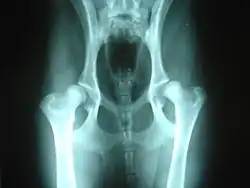

Displasia coxofemoral canina

A displasia coxofemoral é caracterizada por uma instabilidade na articulação coxofemoral (a conexão entre a cabeça do fêmur, ligamento e acetábulo) causando gradual perda da cartilagem e por consequência o desgaste e deformação da cabeça do fêmur e do acetábulo, causando dor e dificuldade de locomoção.[1] Pode ser hereditária ou adquirida.

O diagnóstico é feito pelos sintomas, avaliação clínica, e achados radiológicos.

O grau de displasia, segundo diagnóstico radiográfico, é classificado em 5 graus tomando como base o método de Norberg, conforme a tabela à baixo:[6][7]

| Grau | Descrição | Reprodução |

|---|---|---|

| HD- | Sem sinais de displasia coxofemoral | Apto à reprodução |

| HD+/- | Articulações coxofemorais próximas do normal | Apto à reprodução |

| HD+ | Displasia coxofemoral de grau leve | Ainda permitido |

| HD++ | Displasia coxofemoral de grau moderado | Não apto à reprodução |

| HD+++ | Displasia coxofemoral de grau severo | Não apto à reprodução |

Os graus são nomeados com HD de Hip Dysplasia, em inglês "displasia de anca". Porém os mesmos graus de displasia podem também ser classificados da letra A à letra E, sendo o A equivalente ao grau HD-, e assim consecutivamente.[7]